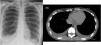

Chest X-ray in the emergency room showed blunting of both costophrenic angles consistent with bilateral pleural effusion (Fig. 1A).

(A) Anterior-posterior chest X-ray at admission showing right pleural effusion and left costophrenic angle blunting. (B) Chest computed axial tomography showing bilateral pleural effusion and pericardial effusion (upper arrow indicates pericardial effusion and the right arrow indicates pleural effusion).

A chest computed tomography angiogram conducted to rule out pulmonary thromboembolism confirmed moderate bilateral pleural effusion with bibasilar and middle lobe atelectasis (Fig. 1B). This was confirmed on chest ultrasound that also ruled out vascular involvement.